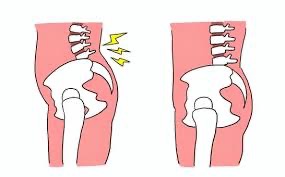

骨盤の前傾

ヒールは骨盤を前に傾ける力が働きます。

いわゆる「骨盤前傾」の状態です。

骨盤が前に傾くと、腰椎(腰の骨)のカーブが強くなり、関節や椎間板(骨と骨の間のクッション)への負担が増します。

ヒールと骨盤のゆがみは切り離せない関係にあります。

ヒールによる腰痛を放置するとどうなるのか?

ヒールによる腰痛を放っておくと、

・慢性腰痛

・坐骨神経痛

・股関節痛

・膝の痛み

などへと広がる可能性があります。